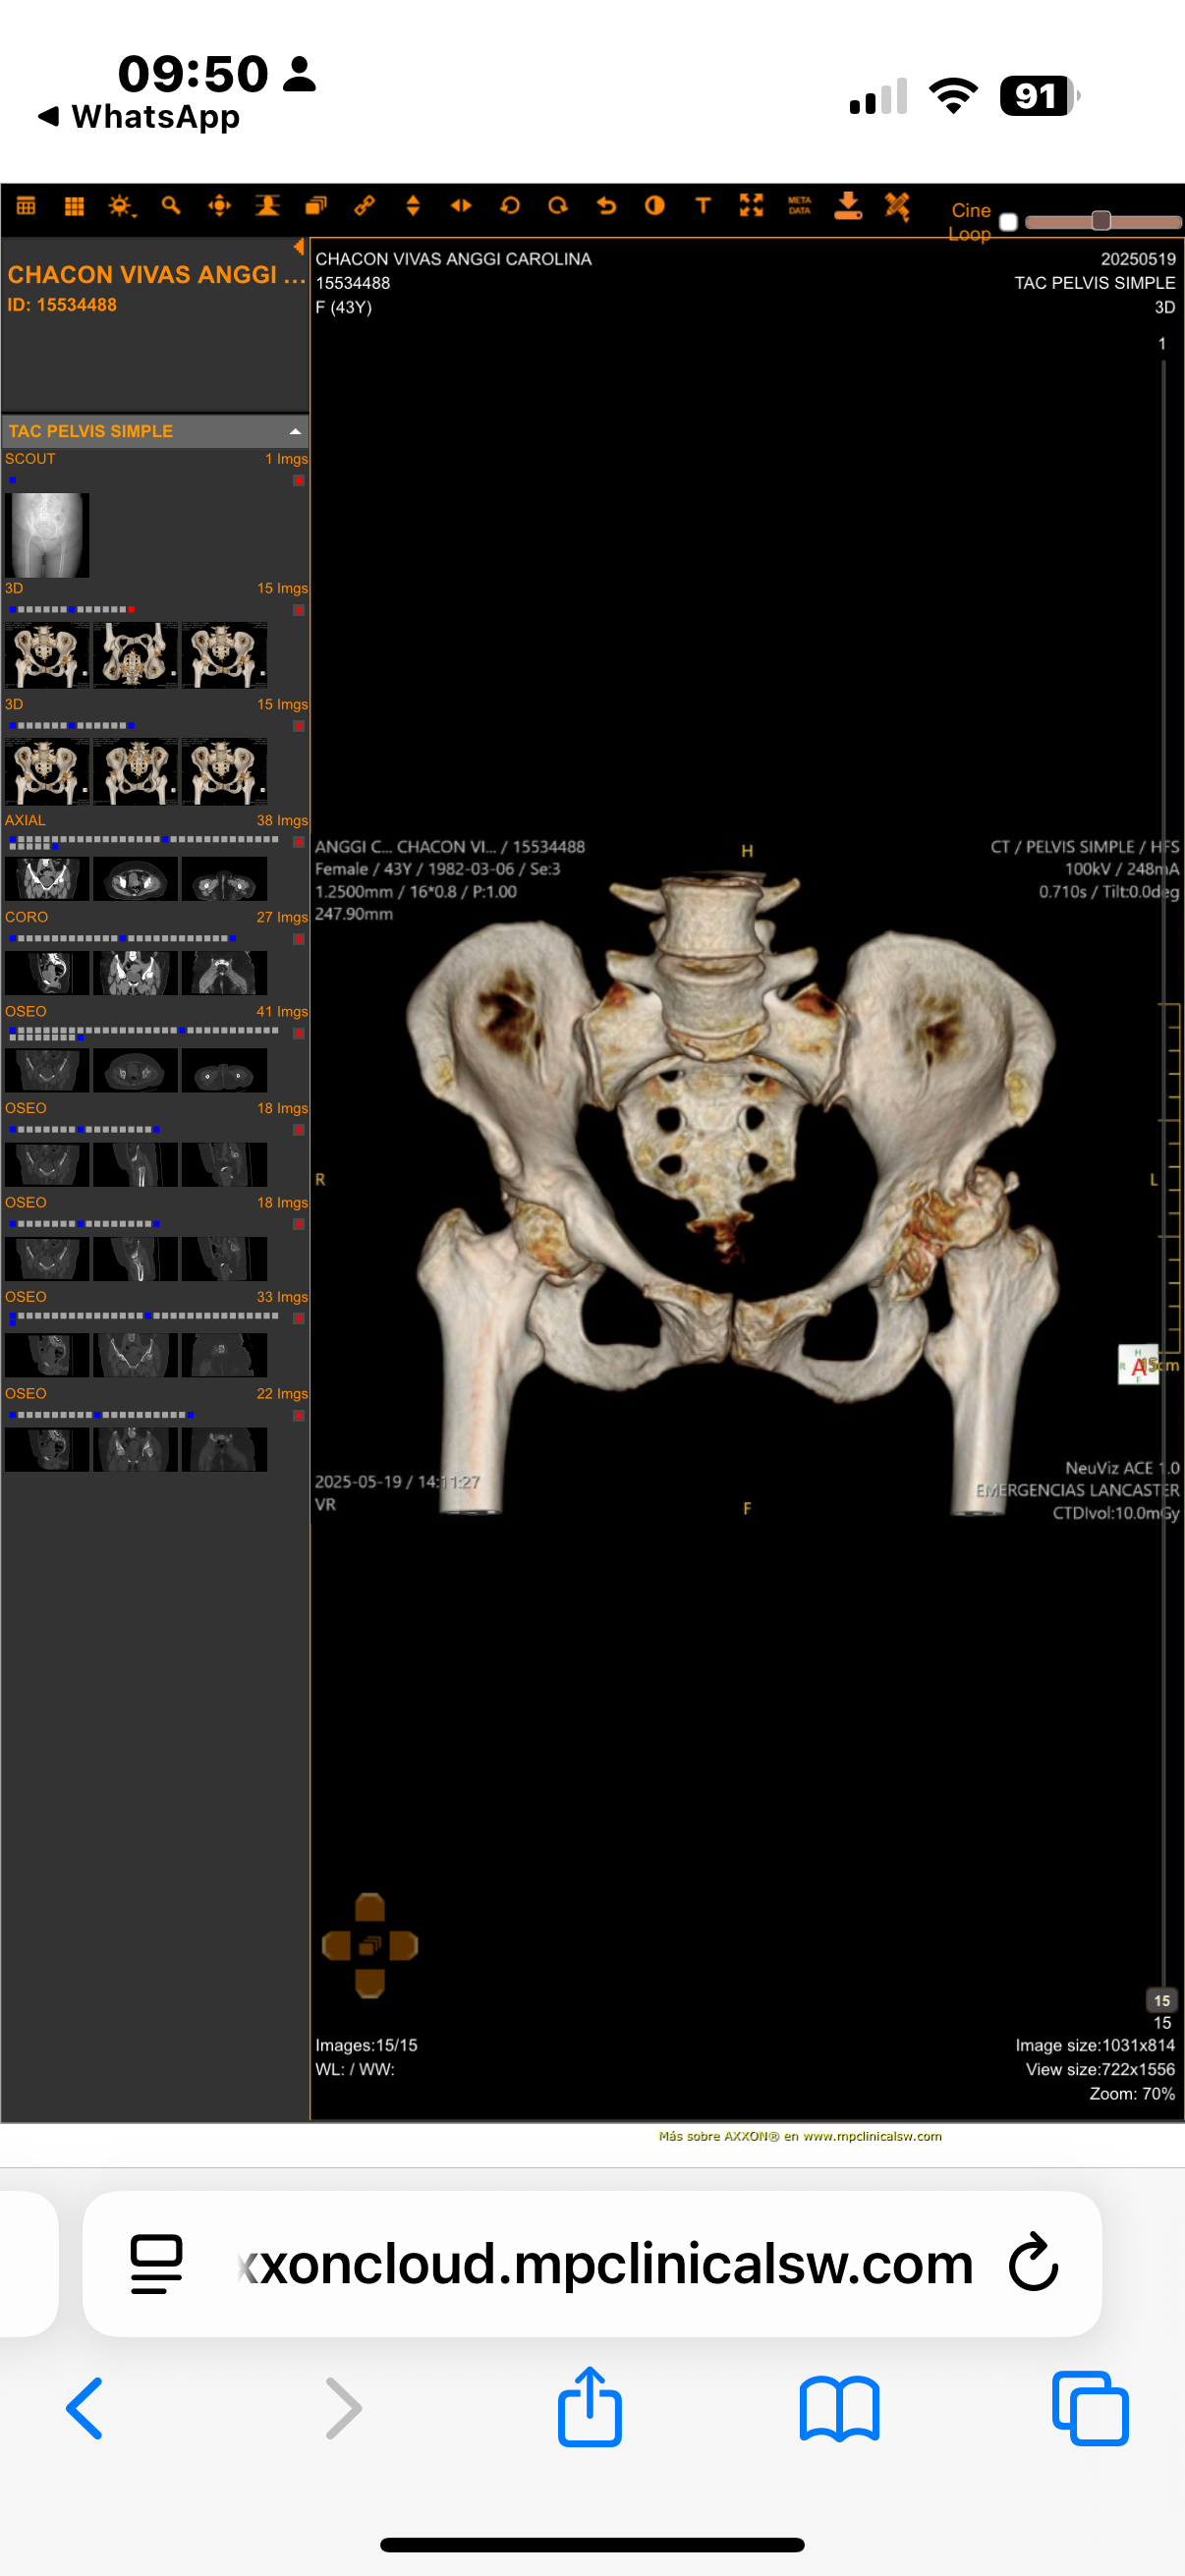

Para quienes deseen ver el informe médico con imágenes, pueden acceder al siguiente enlace:

Este es un visor médico seguro donde se puede observar el daño en la cadera que ha sido evaluado por los especialistas.

For those who wish to see the medical report with images, you can access it through the following link:

This is a secure medical viewer where you can see the damage to the hip as evaluated by specialists.